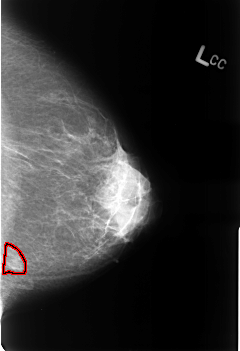

B_3243_1.LEFT_CC

LEFT_CC LINES 4560 PIXELS_PER_LINE 3120 BITS_PER_PIXEL 12 RESOLUTION 50 OVERLAY

FILE: B_3243_1.LEFT_CC.OVERLAY

TOTAL_ABNORMALITIES 1

ABNORMALITY 1

LESION_TYPE MASS SHAPE ASYMMETRIC_BREAST_TISSUE MARGINS N/A

ASSESSMENT 2

SUBTLETY 5

PATHOLOGY BENIGN_WITHOUT_CALLBACK

TOTAL_OUTLINES 1

BOUNDARY